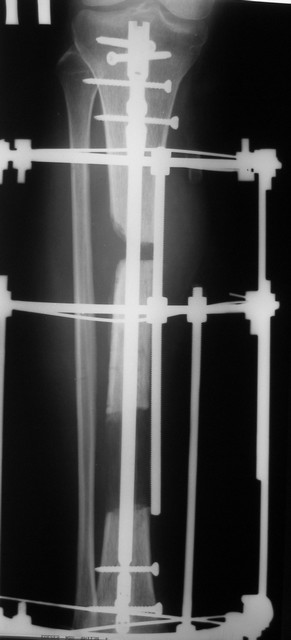

Тогда можно рассмотреть вопрос одновременного удаления штифта, мышечной (в данной области применим проксимально отсеченный лоскут камбаловидной мышцы) или микрохирургической (что более надежно) пластики дефекта мягких тканей, остеотомии проксимального фрагмента большеберцовой кости, остеосинтеза блокируемым штифтом с а/б покрытием, наложения простого аппарата Илизарова (можно из полуколец) для дистракции на штифте. При данном варианте пациент сохраняет возможность полной опоры на ногу, что очень важно для заживления у пожилого пациента) и отпадает необходимость в проведении дополнительный операций (при благоприятном развитии событий).

Выкладываю картинки похожей пациентки. Извините, что без окончательных снимков (сейчас их нет под рукой). Правда мы имели проблемы у данной больной после снятия аппарата, когда промежуточный фрагмент большеберцовой кости сместился на 1,5 см дистально и отошел от проксимальной части кости. До сих пор у пациентки на снимках определяется лишь тонкая полоска кости по задней поверхности за штифтом (образовалось что-то вроде маленького регенерата)в области стыковки промежуточного и проксимального фрагментов. Большая пока решила подождать. Не хочет оперироваться, так как ходит не хромая, работает.